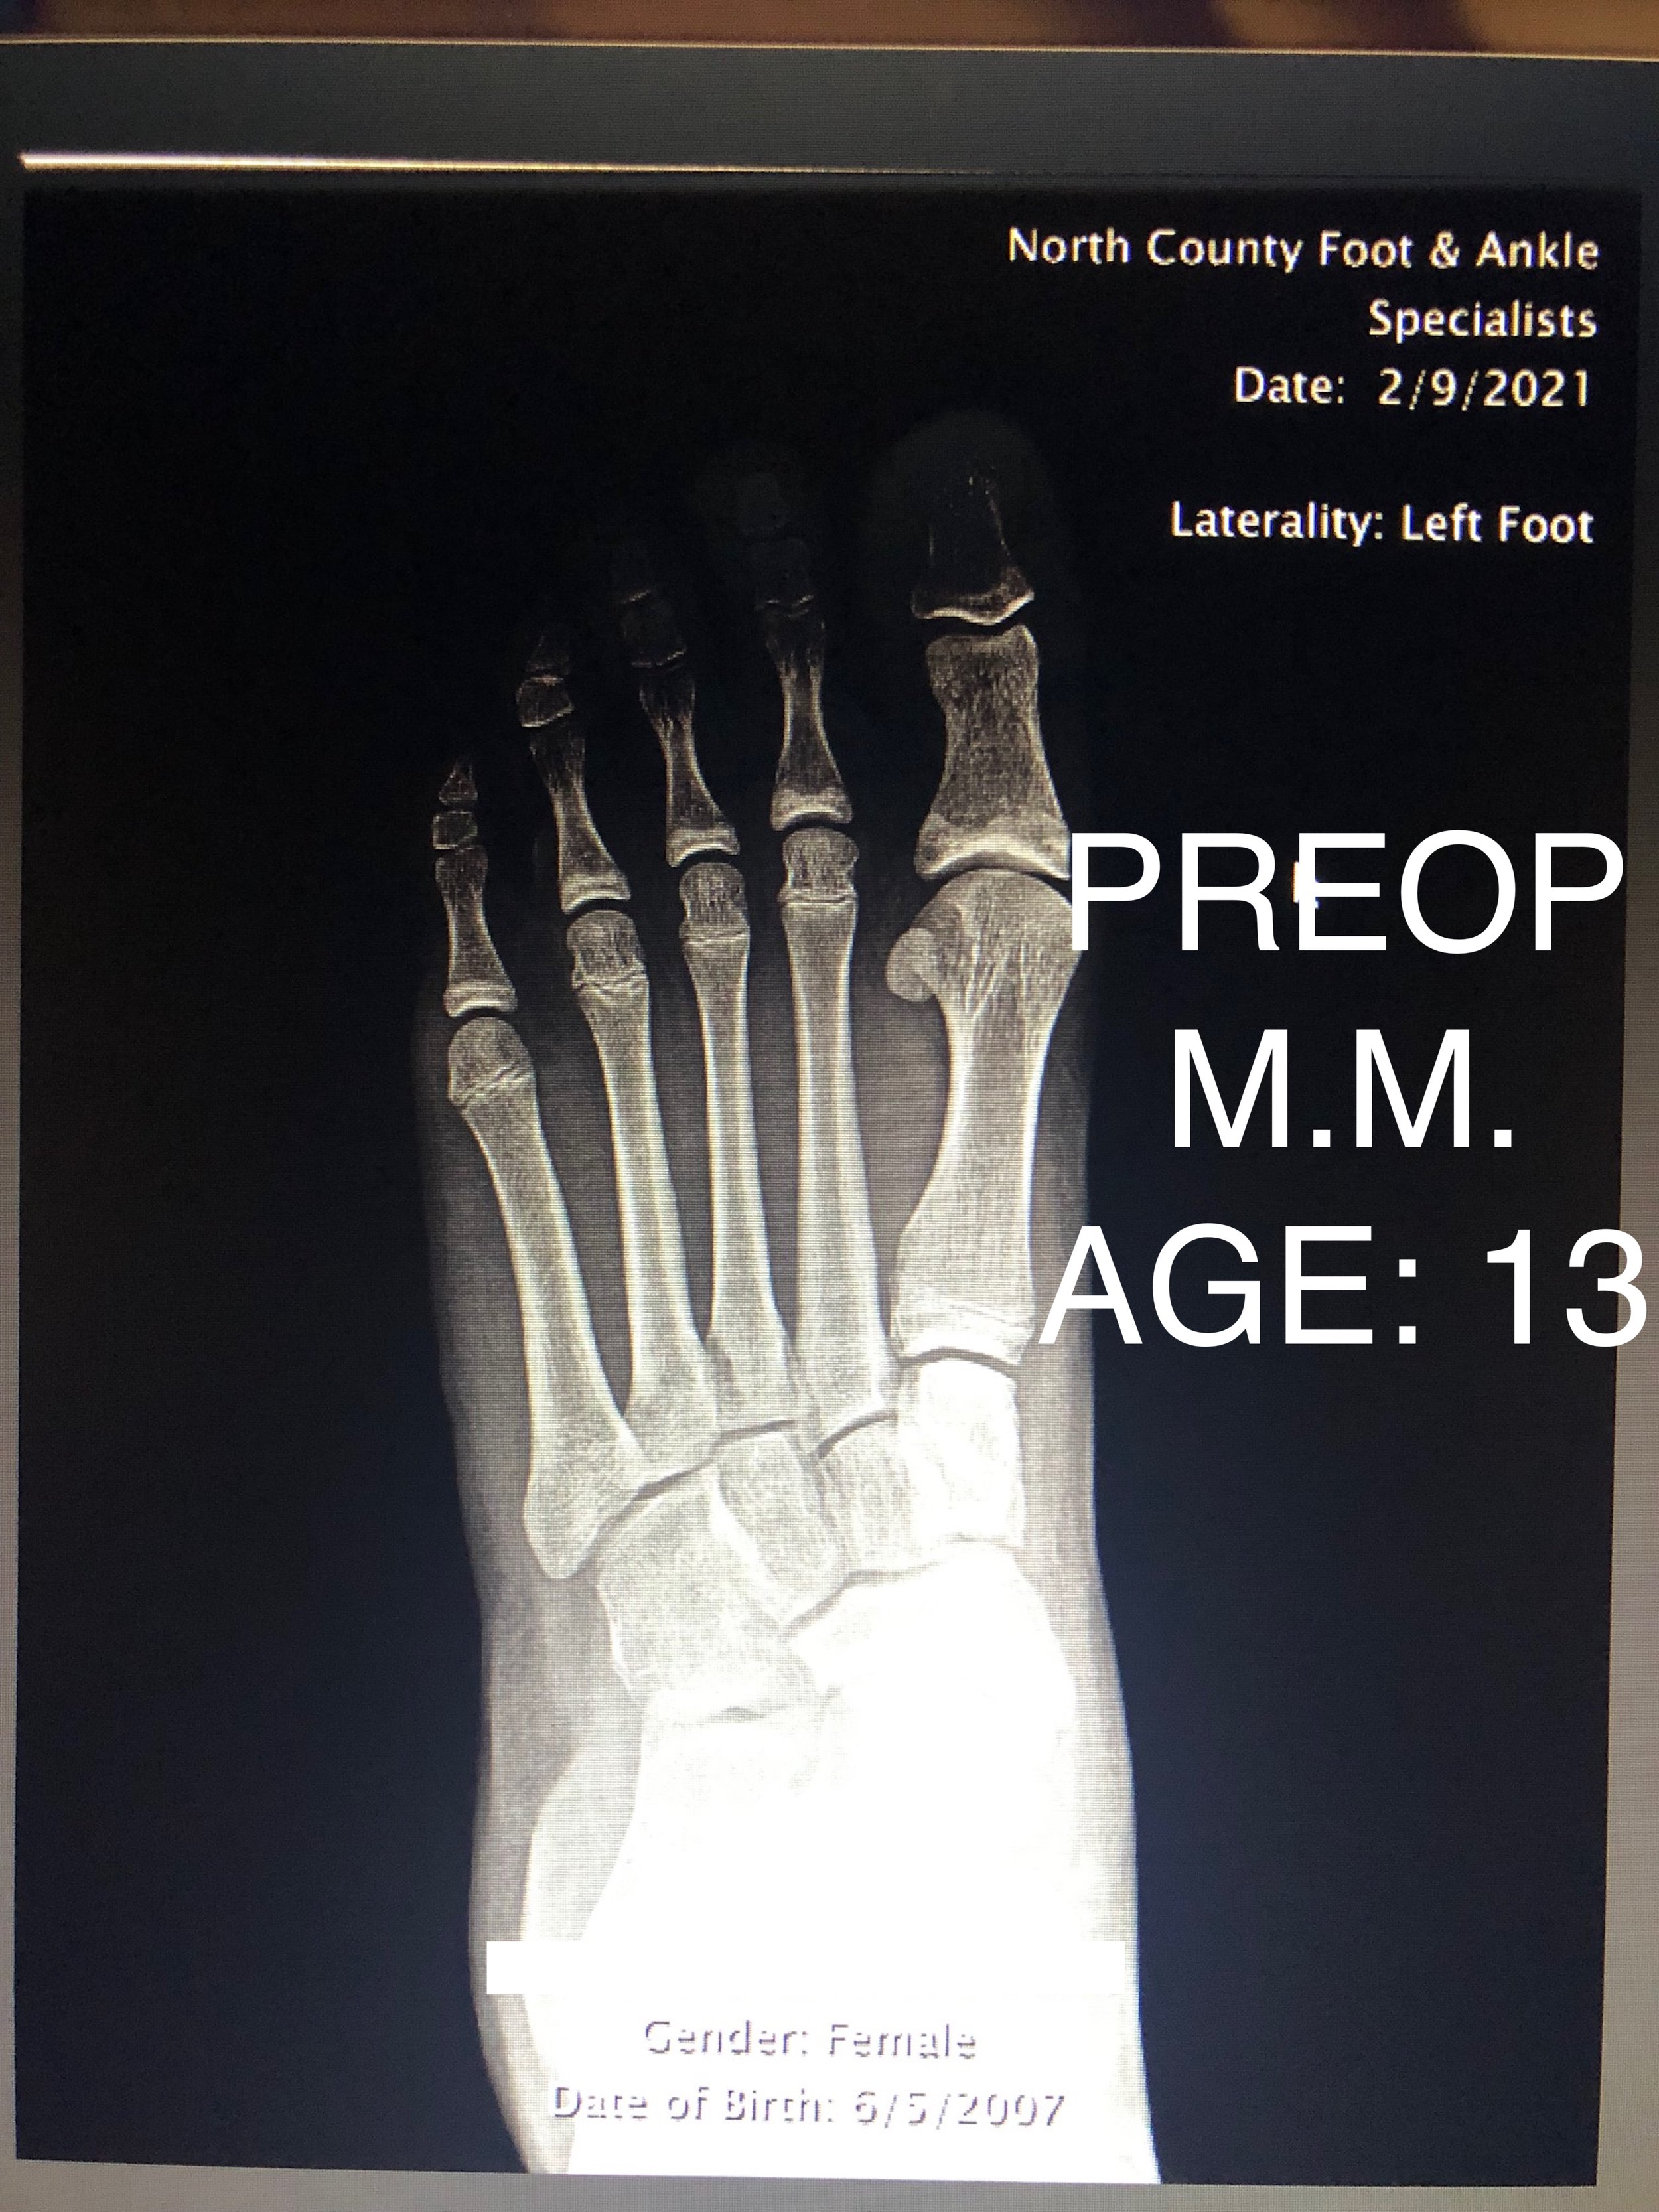

LAPIDUS